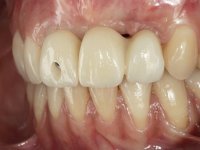

The surgical implant exposure and the healing screw placement proved to be a negative surprise regarding its position. Since the proposed removal of the implant was refused, we advanced to its provisional rehabilitation. An open tray impression technique was done, and a screwed abutment with a coronal and gingival component and an acrylic crown were made in the laboratory, using these two components. The provisional crown was placed in the mouth until a final decision was made. Six years passed before the patient returned to the clinic with an abscess on tooth 1.1. The choice to remove teeth 1.1 and 2.2 was made, to create a provisional 3-element bridge with a net to be adhered to the adjacent teeth. Surgery was planned and performed, placing the two implants at the site of 1.1 and 2.2, and the implant at the 2.1 site was cut with the objective of submerging it, while adequate tissue regeneration was performed (Surgical Work performed By Dr. Manuel Neves). During osseointegration, the patient used the fixed provisional bridge. A first impression was made for confection of a zirconia screwed provisional bridge, which worked the soft tissues for twelve weeks. The definitive impression was made with the individualisation of custom impression copings. Final rehabilitation was done with ceramized abutments, and also a bridge with zirconia infrastructure and ceramic cover. Due to the inclination of the implant placed at the site of tooth 1.1, the bridge required cemented fixation.